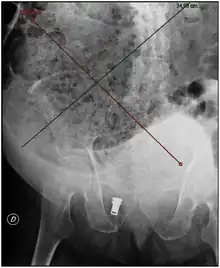

| Plain abdominal X-ray showing a large fecal impaction extending from the pelvis upwards to the left subphrenic space and from the left towards the right flank, measuring over 40 cm in length and 33 cm in width. | |